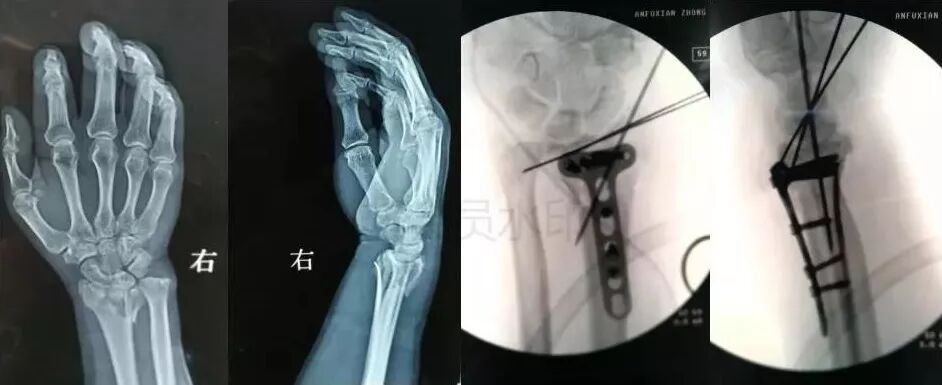

7)手部骨折

图片

• 无论闭合或开放性骨折,均应早期复位内固定。

• 合并神经,血管,肌腱损伤,紧急手术。